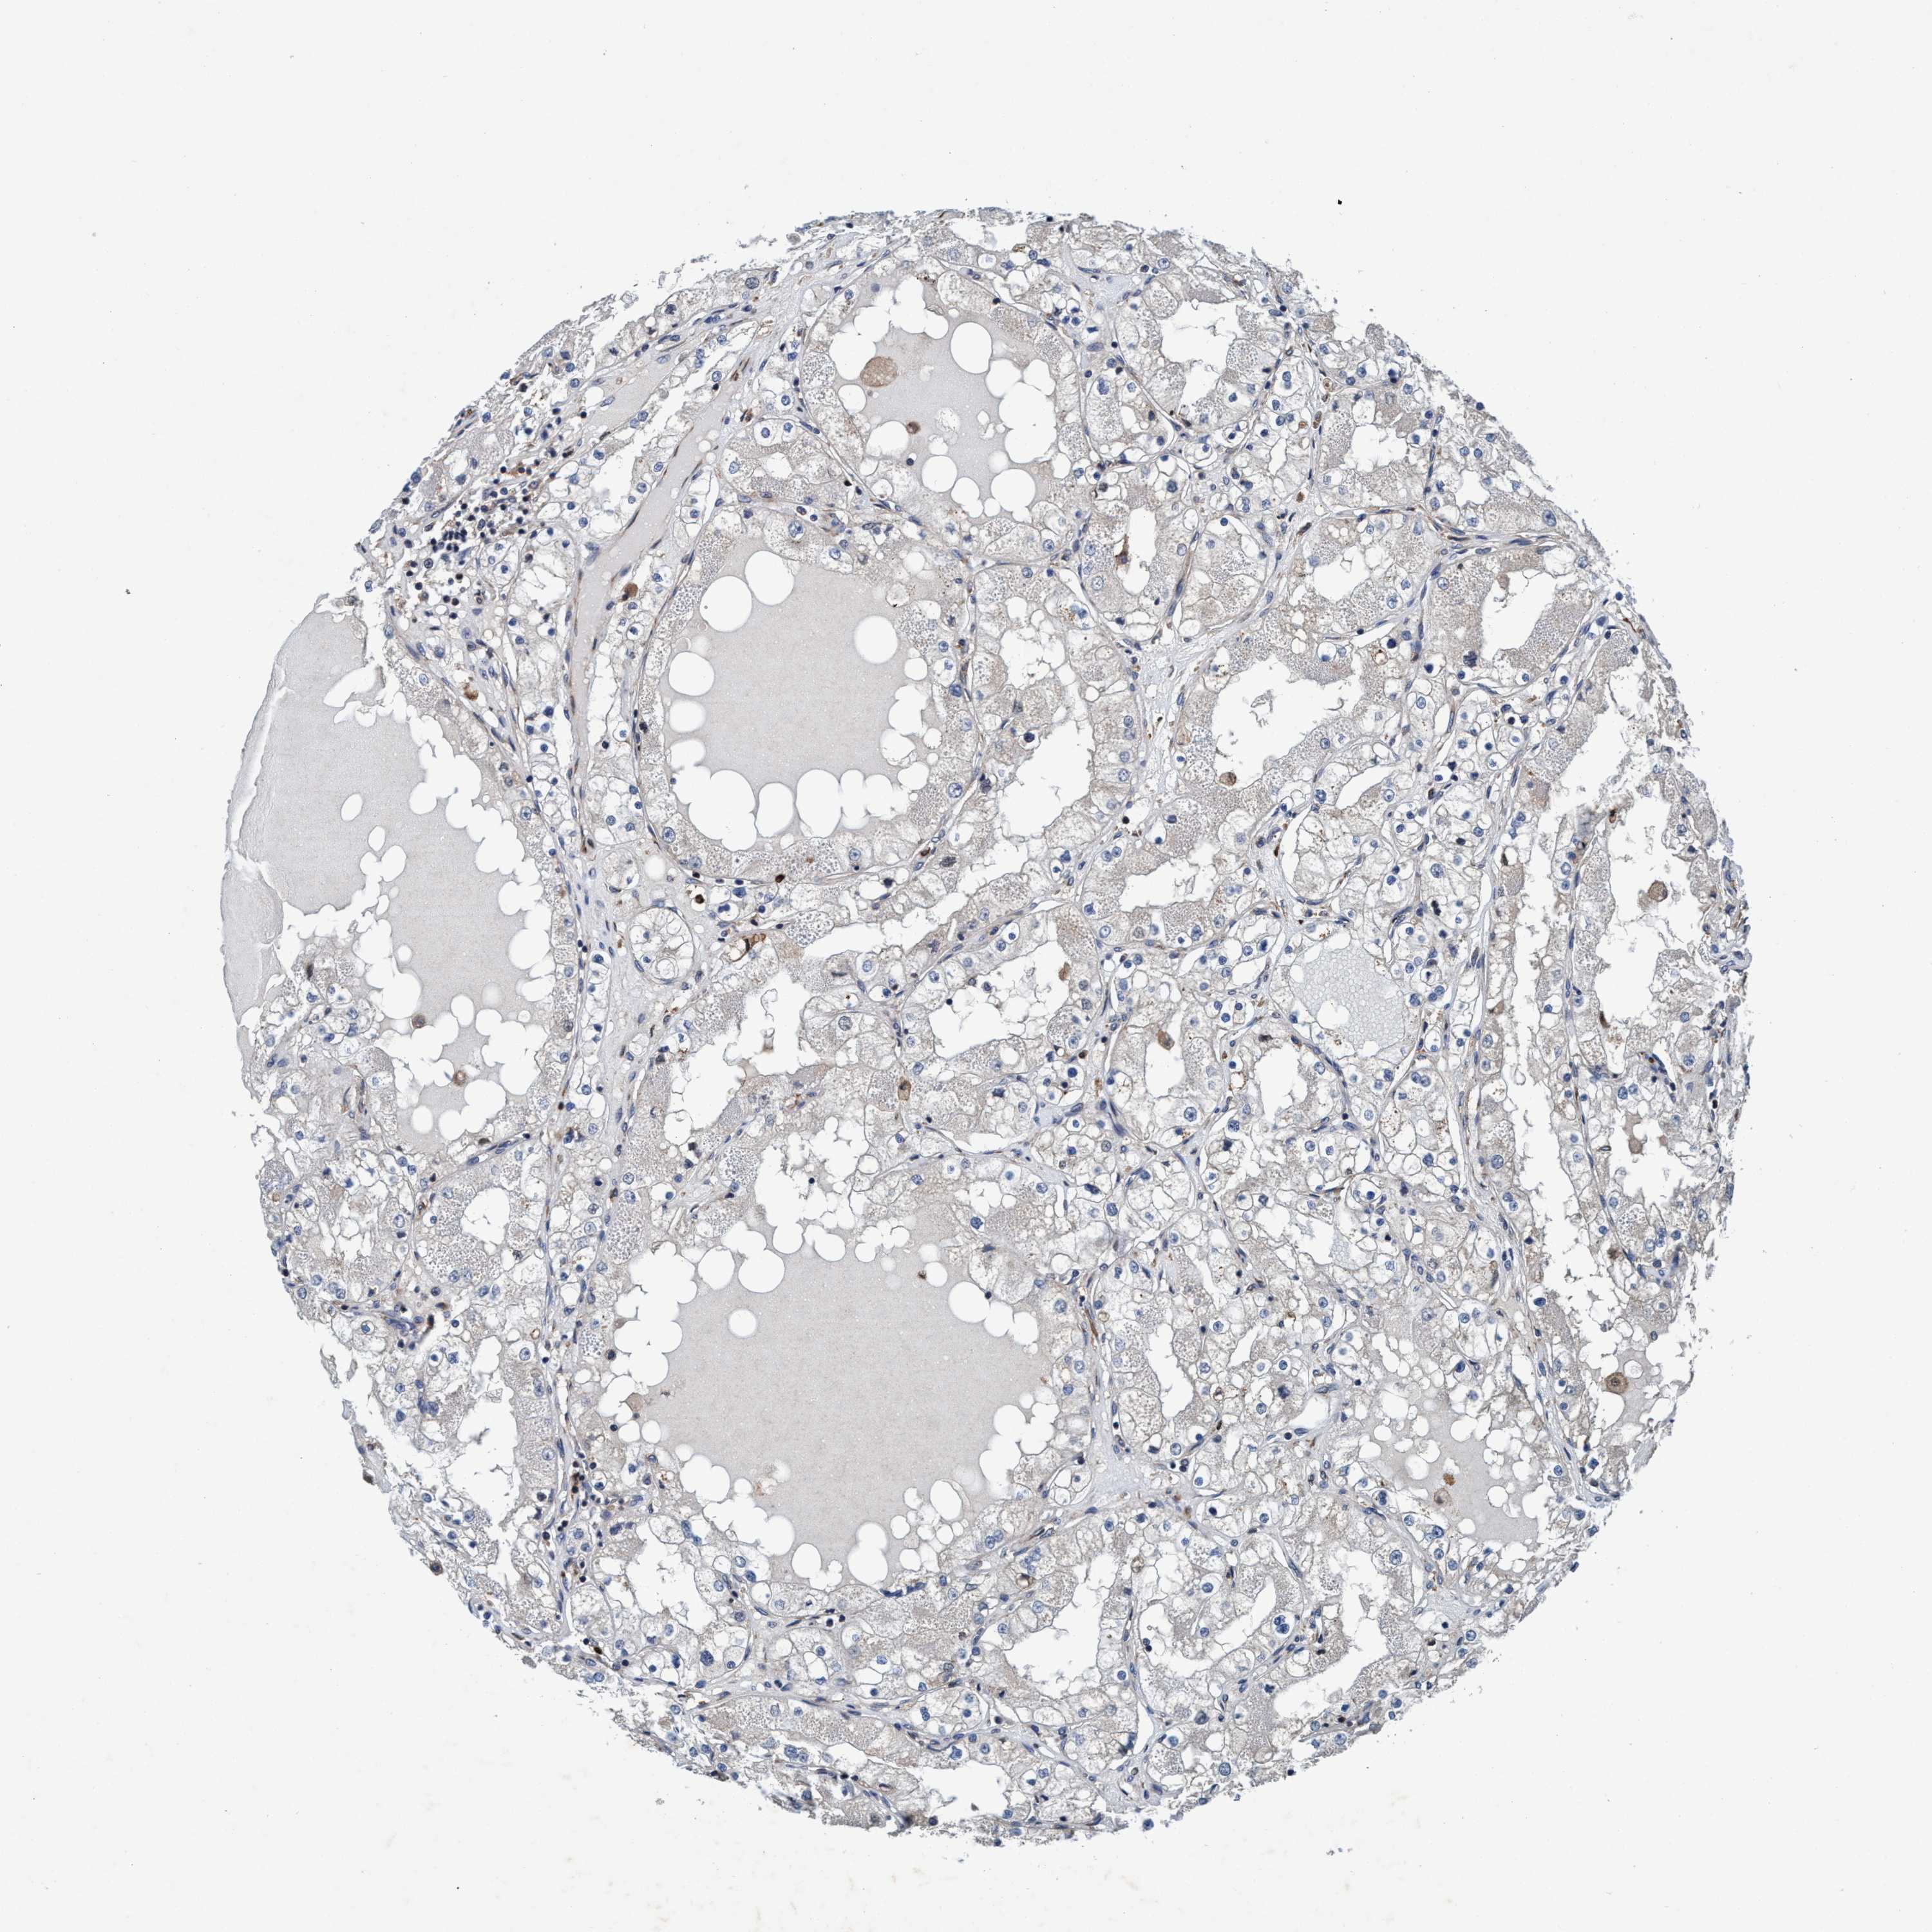

KIDNEY RENAL CLEAR CELL CARCINOMA (TCGA) - Interactive survival scatter ploti

ENDOG is not prognostic in Kidney Renal Clear Cell Carcinoma (TCGA)

: 13.15

Average pTPM 11.9

Number of samples 521